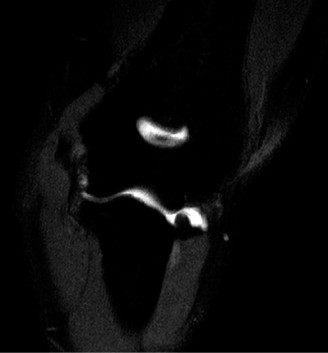

The patient undergoes conservative management consisting of rest, anti-inflammatory medications, and physical therapy. After six months, he is still not able to return to play and has progressively worsening symptoms with attempted throwing. He has a moderate elbow effusion as well as a 20-degree flexion contracture. An elbow MRI arthrogram is obtained and shown (Fig. 2–112). He elects to proceed with elbow arthroscopy. Intraoperative arthroscopic images are shown (Figs. 2–113 and 2–114).

Figure 2–112

Figure 2–113

Figure 2–114

Which of the following is the most commonly reported complication of elbow arthroscopy?

- Contracture

- Compartment syndrome

- Septic joint

- Neuropraxia

- Vessel injury

Discussion

The correct answer is (D). The overall reported rate of transient and permanent complications after elbow arthroscopy is around 10% and is much higher than the rate after knee and shoulder arthroscopy (1–2%). The overall most commonly reported complication is prolonged drainage or erythema around portal sites. The lateral portal sites are susceptible to this issue as the joint is relatively subcutaneous in this area, and there is scant tissue to act as a barrier. Deep infection, while being the most serious postoperative complication, is relatively rare (0.8%). In one series, the rate of transient neurological injuries was found to be 2%. These result from compression, local anesthetic injection, and direct trauma. A thorough understanding of the neurovascular anatomy of the elbow is crucial to achieve proper portal placement. Loss of elbow motion was reported in approximately 1% of cases and is usually minor (less than 20 degrees). Objectives: Did you learn...? Recognize the clinical and radiographic presentation of elbow osteochondritis dissecans?